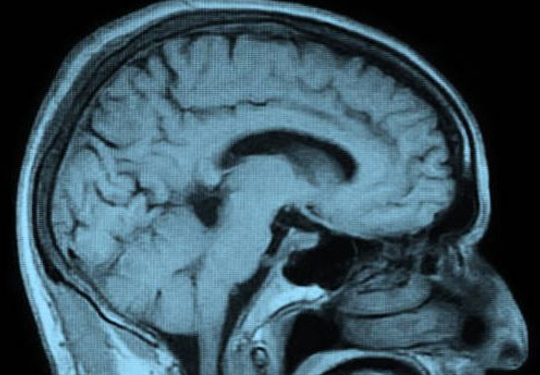

Normal Brain MRI

A routine MRI of the brain, even a contrast study, does not adequately evaluate for concussion or blast brain injury. Many times, a brain MRI that is done without special applications is interpreted as normal or normal for age but there is actually significant brain injury.